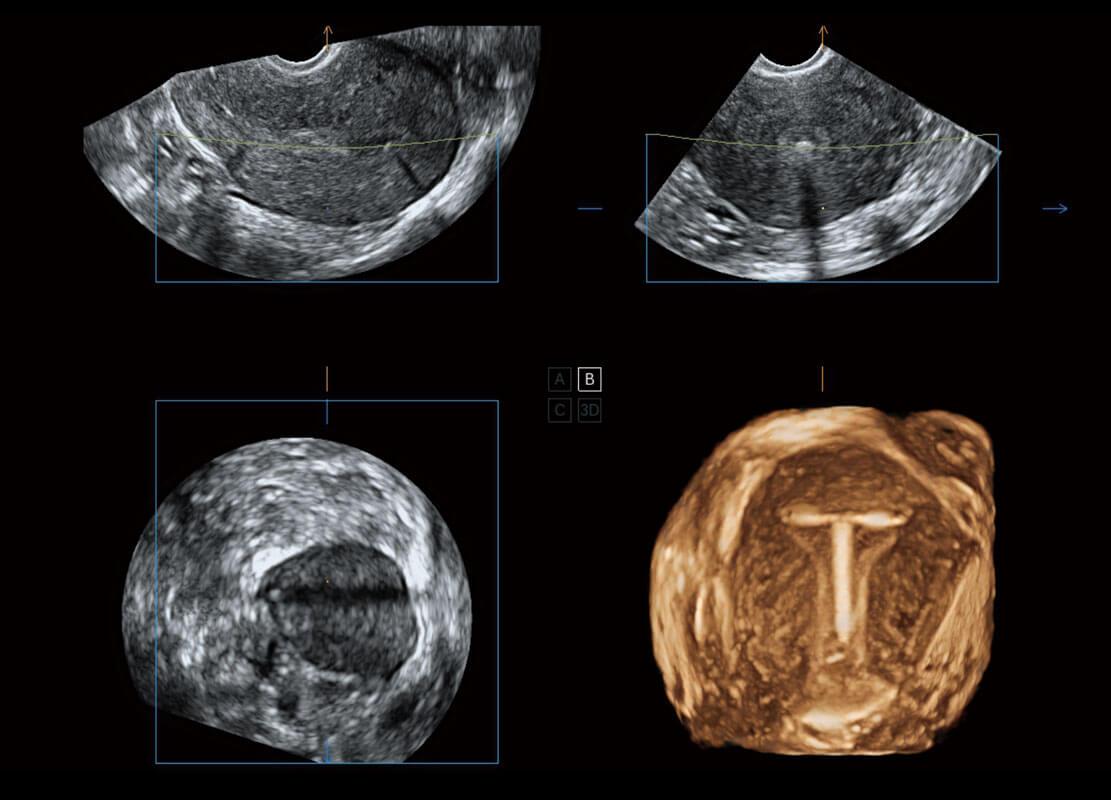

腔内三维-宫内节育器